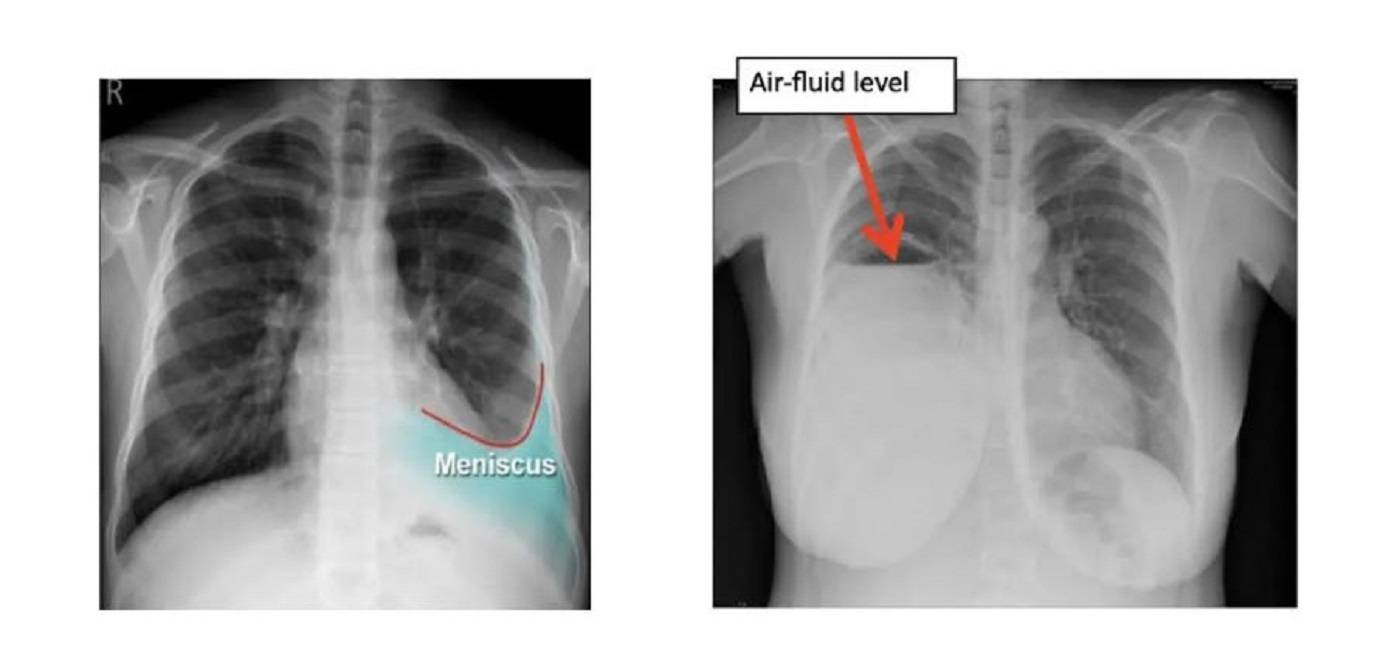

ในกลุ่มที่สองเกิดจากตัวปอดเอง (Exudative Pleural Effusion) ซึ่งมักจะเกิดจากมะเร็ง (เช่น มะเร็งปอด, มะเร็งเต้านมกระจายมาที่เยื่อหุ้มปอด), วัณโรคปอด (Tuberculosis), ปอดติดเชื้อ (Pneumonia) อันเกิดจากเยื่อหุ้มปอดอักเสบหรือมีการอุดตันของระบบน้ำเหลือง รวมถึงของเหลวที่มีโปรตีนสูงและเซลล์อักเสบจำนวนมาก โดยการรักษานั้น หากเกิดจากมะเร็งเราสามารถเอาน้ำออกแล้วใส่ยาเคลือบปอดเพื่อป้องกันการกลับมาเป็นซ้ำได้ (chemical pleurodesis) และในส่วนของกลุ่มที่เกิดภาวะติดเชื้อ เช่น วัณโรคหรือปอดติดเชื้อ หากดำเนินการรักษาแก้อาการของตัวโรค โดยลดอาการบวมน้ำลง อาการก็มักจะดีขึ้นตามมา แต่อาการที่พบในผู้ป่วยอยู่บ่อยครั้ง เช่น มีอาการหายใจลำบาก, มีภาวะเจ็บหน้าอก (โดยเฉพาะเวลาหายใจลึก ๆ) หรือไอแห้ง ๆ มีน้ำเสียงลดลง เหล่านี้แพทย์มักจะวินิจฉัยว่าเกิดจากน้ำในเยื่อหุ้มปอด ซึ่งสามารถใช้การเอกซเรย์ทรวงอก, อัลตราซาวด์ หรือ CT scan และอาจมีการเจาะน้ำในเยื่อหุ้มปอด เพื่อนำไปตรวจหาสาเหตุที่แน่นอน ทั้งนี้การวินิจฉัยน้ำในเยื่อหุ้มปอดนั้น สามารถนำหลักการรักษาน้ำในเยื่อหุ้มปอดให้เป็นปกติได้โดย 1.รักษาตามสาเหตุที่ทำให้เกิดน้ำที่ทำให้เกิดภาวะหัวใจวาย(CHF) โดยส่วนใหญ่จะให้ยาขับปัสสาวะเพื่อลดน้ำในร่างกาย แต่หากผู้ป่วยเป็นวัณโรค ก็จะให้ยาต้านวัณโรคครบสูตร 6-9 เดือน ส่วนผู้ป่วยที่ป่วยเป็นโรคมะเร็ง แพทย์ผู้รักษาจะพิจารณาให้เคมีบำบัด ทำการระบายของเหลวร่วมกับใส่สารเคลือบเยื่อหุ้มปอด(Pleurodesis) เพื่อป้องกันการกลับมาเป็นซ้ำ ส่วนอีกอาการหนึ่งคือ หากเกิดอาการติดเชื้อ เช่น เกิดภาวะปอดบวม แพทย์ผู้ทำการรักษาจะให้ยาปฏิชีวนะร่วมด้วย